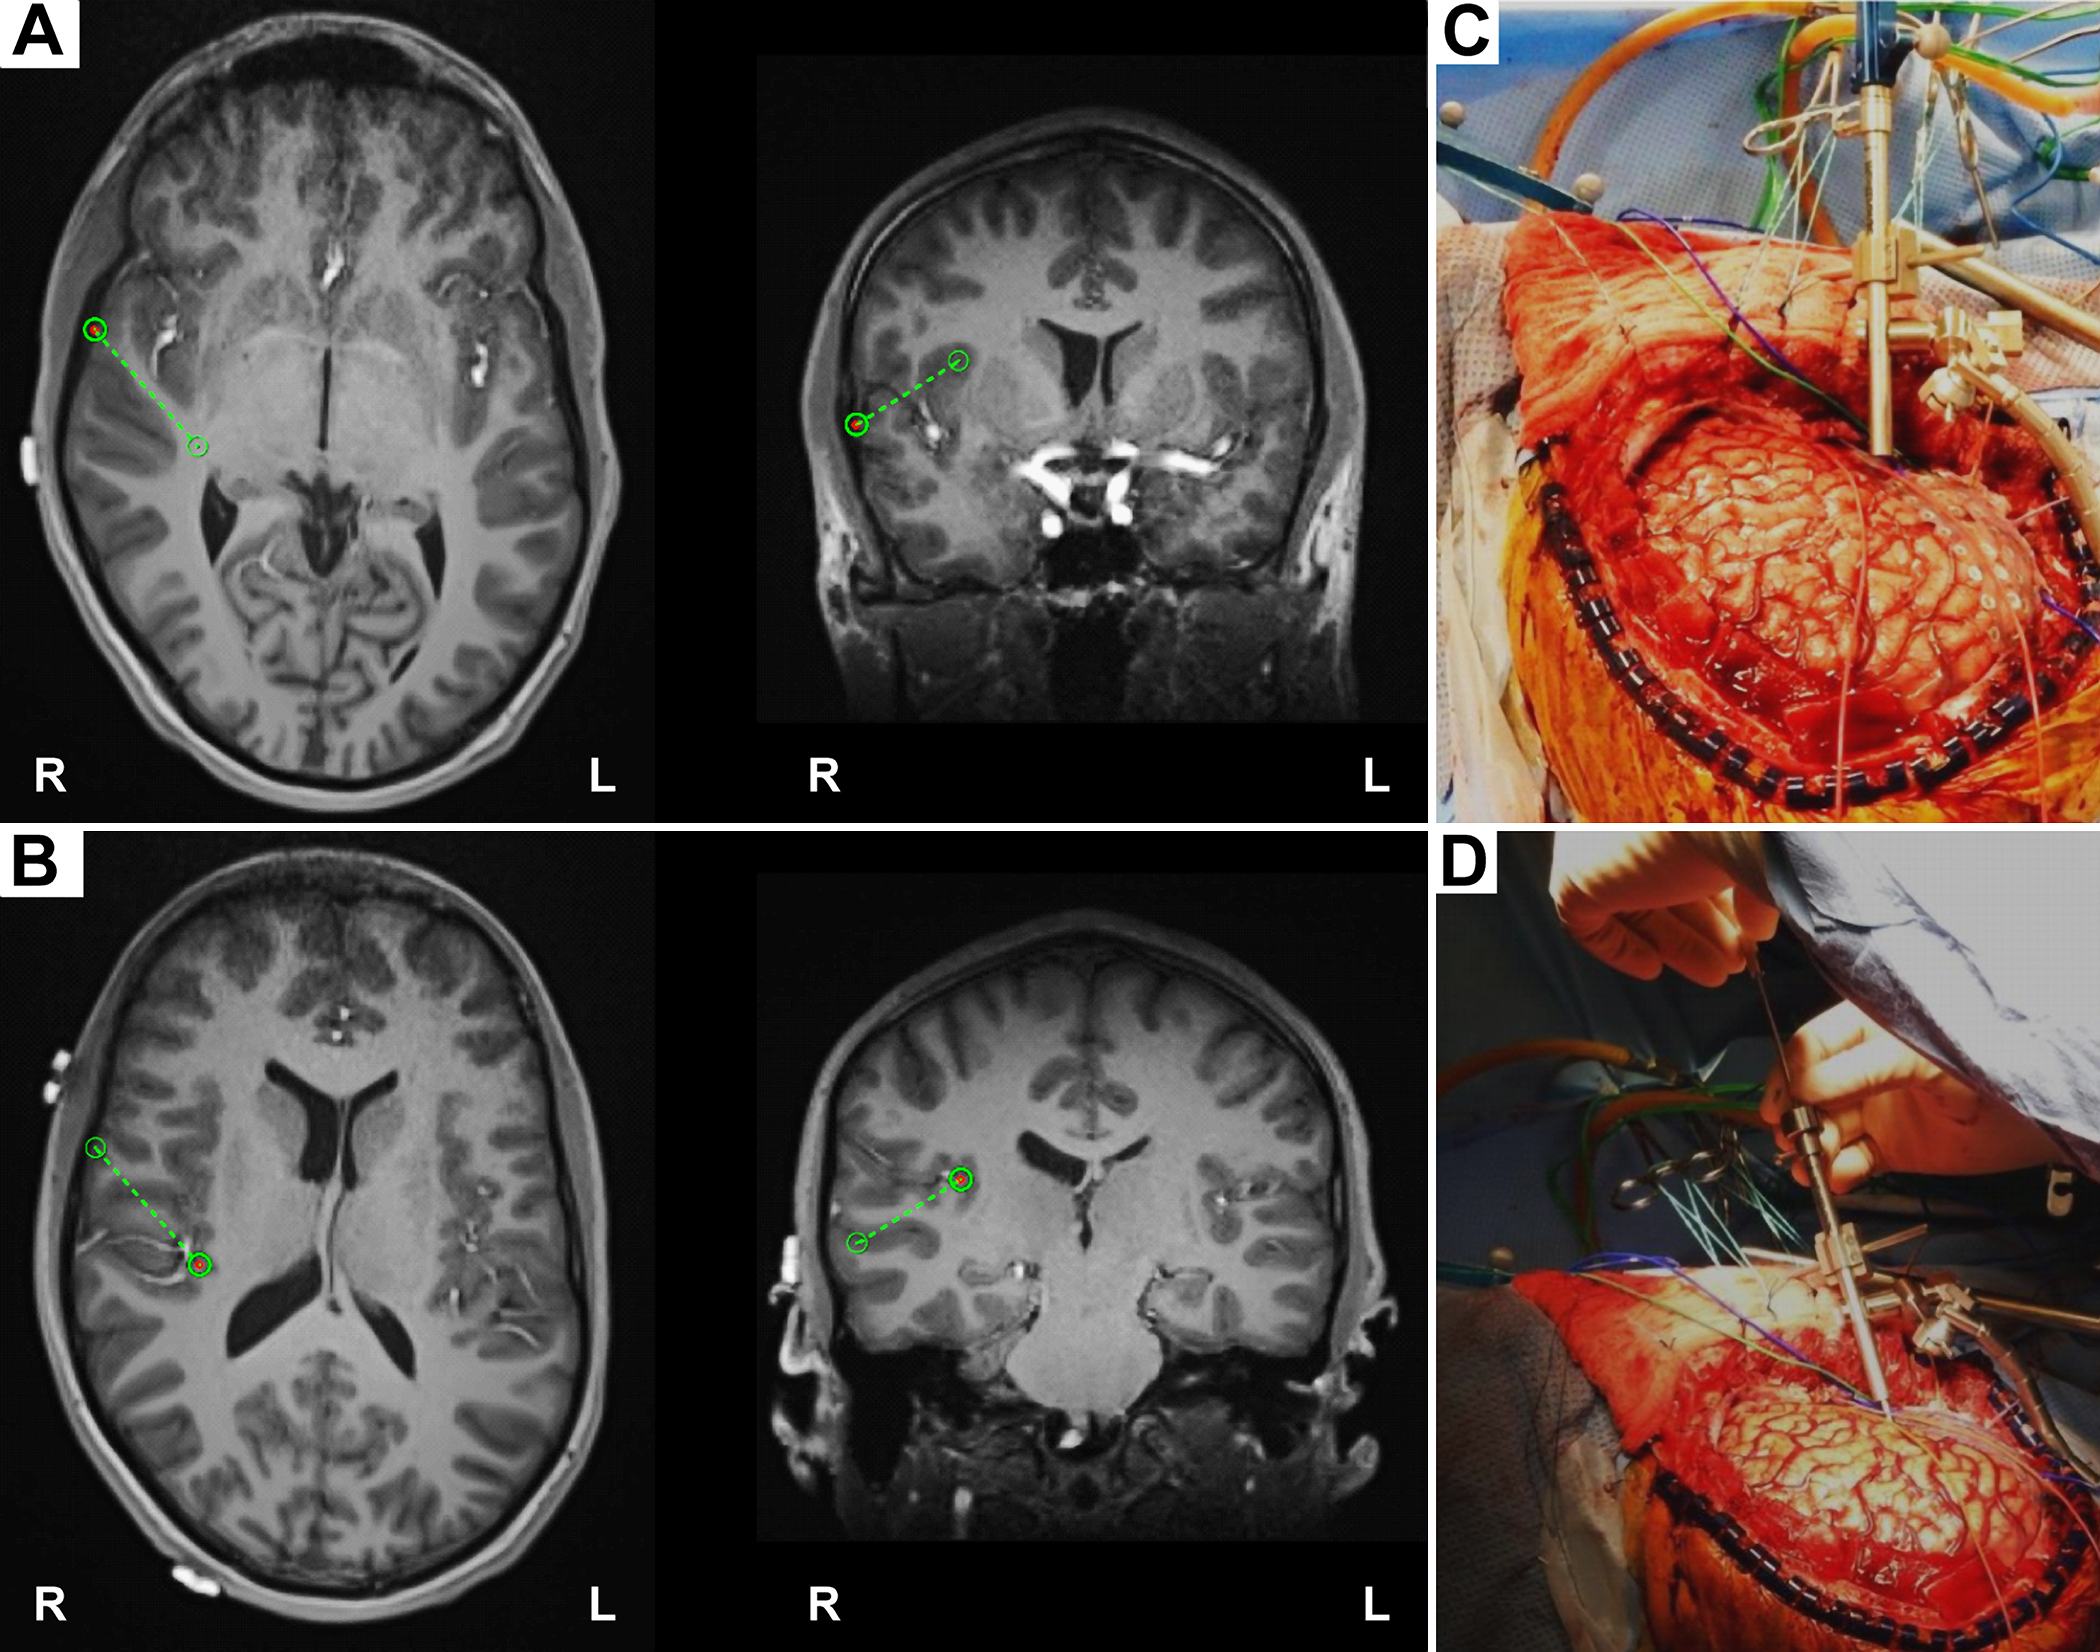

We can see how the endocranial EEG looks and how it gets done (WARNING: GRAPHIC) by referring to Nagahama et al (2019):

Intraoperative photographs demonstrating exposure and intracranial electrode placement. A right frontotemporoparietal craniotomy (A) allowed proper exposure for placement of grid, strip, and depth of electrodes (B), including the HG depth electrode. The sylvian fissure is marked with a dashed line. The HG depth electrode and PT depth electrose are marked with X symbols anteriorly and posteriorly, respectively, at their entry points at the cortical surface. Ant = anterior; inf = inferior; post = posterior; sup = superior.

Intraoperative placement of the HG depth electrode. A: The planning view on the frameless stereotactic system (Stealth Navigation, Medtronic) showing the entry point and the trajectory (green circles and dotted lines). B: The similar planning view showing the target and the trajectory. C and D: Intraoperative photographs showing placement of the HG depth electrode. A Stealth Navigus probe was used to select the appropriate trajectory of a guiding tube positioned over the entry point (C). An electrode-guiding cannula was advanced through the tube to the previously determined depth (D). An actual depth electrode was subsequently passed through the cannula, followed by removal of the guiding tube/cannula system. Note the unique anterolateral-to-posteromedial trajectory within the STP for placement of the HG depth electrode.